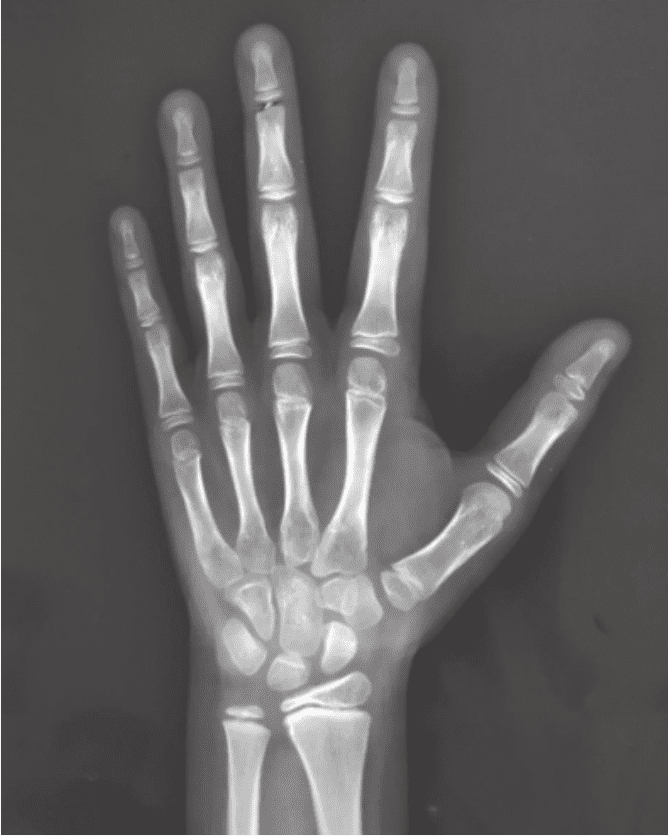

看孩子骨生理年齡一般要拍X片來進行判斷。如果孩子是右利手,那么在拍片子的時候要拍左手;如果孩子是左撇子,那就要拍右手,這樣得到的結果會更可靠。如果年齡到了一定程度,還要拍其他的部分,比如腳后跟、肘關節(jié)、骨盆等。

骨生理年齡X片

拍片的作用是了解孩子真正的發(fā)育水平,預測孩子成年的身高。判斷骨生理年齡有很多方法,但是很遺憾,目前全世界還沒有一個大家都普遍認可的精準方法。

在北京協(xié)和醫(yī)院,一般比較推崇的是圖譜法。根據(jù)圖譜,我們倒推骨生理年齡的情況,再結合生長發(fā)育的整體情況,測算他的骨骼到底處于生長發(fā)育的什么階段。這對于我們來說是一個非常重要的手段。當然,這個計算過程比較煩瑣,我們一般會借助專門的計算機系統(tǒng)來進行輔助分析。父母可能沒辦法計算清楚,但可以請大夫根據(jù)骨生理年齡片子幫忙計算。